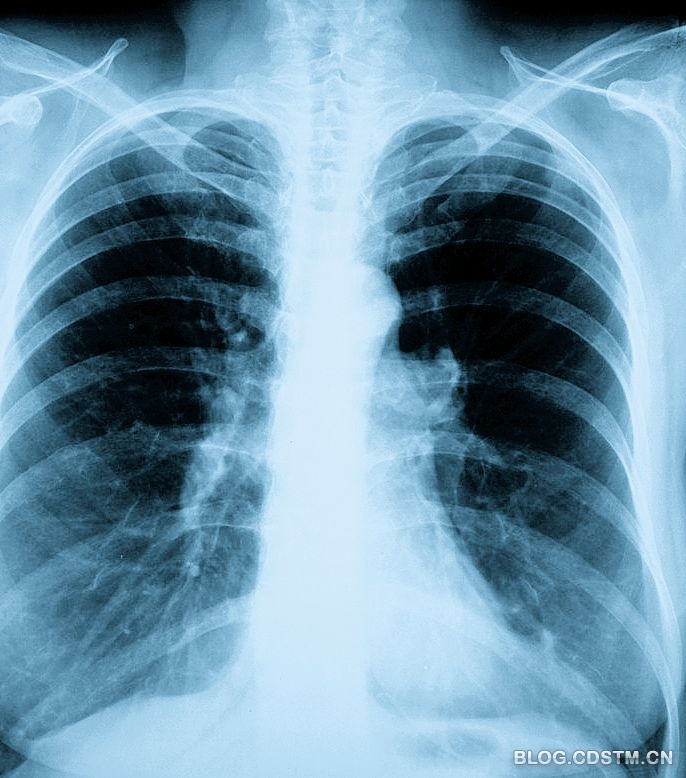

再比如肺癌,有报告显示,一个人近亲中有得肺癌的,而他又吸烟,则其肺癌风险比一般人高14 倍;乳腺癌也有一定的遗传倾向,如母亲是乳腺癌患者,其女儿发病机会比一般女性高3 倍。母亲50 岁左右绝经前患双侧乳腺癌的,下一代乳腺癌发病率较高;而像你朋友父亲这样的肝癌病人,一般如果父母被查出肝癌,那子女是一级预防对象,因为乙肝的垂直传播易造成肝癌的家族聚集倾向。特别是携带乙肝病毒的母亲,其后代发生肝癌几率较高。